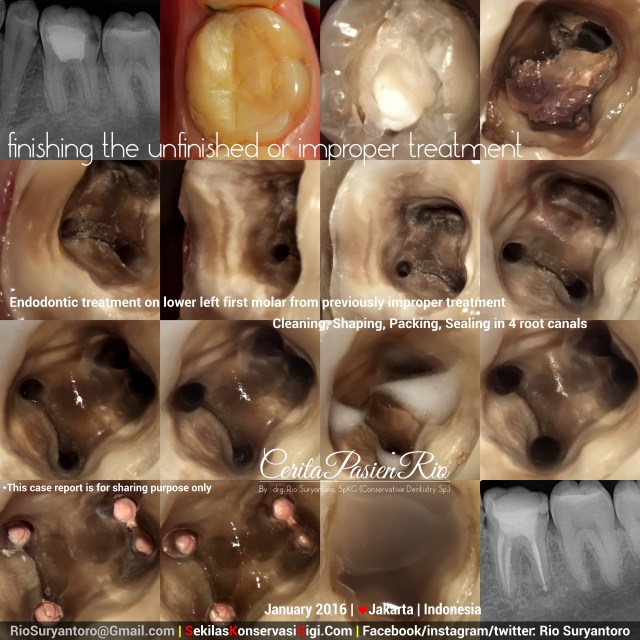

I got this case referral from my friend (dentist), drg. Natalia Astina, because she suspected a perforation in bifurcation under improper treatment (from xray image). The patient itself had undergone this kind of dental treatment for 1,5 years, and now he got his tooth ache and want to get it repaired.

There was an overhanging and improper composite resin restoration, and when i tried to remove it, i found a thick ZOE base. Plus remnants of infected dentine & pulp stone at the pulp chamber.

After rebuild up the cavity using composite resin and universal matrix, i did endodontic treatment in one visit for those 4 canals with ProtaperNext (Dentsply) and seal it with flowable composite SDR (Dentsply).